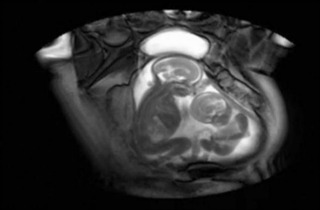

Newly Developed MRI Scan Shows Twins Fighting Inside The Womb

Anjali SareenDec 1st